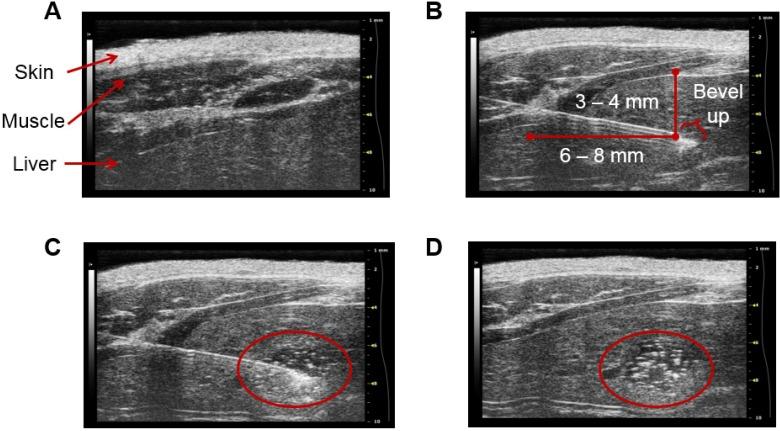

A common form of treatment for patients with hepatocellular carcinoma (HCC) is transarterial radioembolization (TARE) with non-degradable glass or resin microspheres (MS) labeled with Y (Y-MS). To further simplify the dosimetry calculations in the clinical setting, to have more control over the particle size and to change the permanent embolization to a temporary one, we developed uniformly-sized, biodegradable Re-labeled MS (Re-MS) as a new and easily imageable TARE agent. MS made of poly(-lactic acid) were produced in a flow focusing microchip. The MS were labeled with Re using a customized kit. An orthotopic HCC animal model was developed in male Sprague Dawley rats by injecting N1-S1 cells directly into the liver using ultrasound guidance. A suspension of Re-MS was administered via hepatic intra-arterial catheterization 2 weeks post-inoculation of the N1-S1 cells. The rats were imaged by SPECT 1, 24, 48, and 72 h post-radioembolization. The spherical Re-MS had a diameter of 41.8 ± 6.0 µm ( = 14.5%). The site and the depth of the injection of N1-S1 cells were controlled by visualization of the liver in sonograms. Single 0.5 g tumors were grown in all rats. Re-MS accumulated in the liver with no deposition in the lungs. Re decays to stable Os by emission of β particles with similar energy to those emitted by Y while simultaneously emitting γ photons, which were imaged directly by single photon computed tomography (SPECT). Using Monte Carlo methods, the dose to the tumors was calculated to be 3-6 times larger than to the healthy liver tissue. Re-MS have the potential to become the next generation of β-emitting MS for TARE. Future work revolves around the investigation of the therapeutic potential of Re-MS in a large-scale, long-term preclinical study as well as the evaluation of the clinical outcomes of using Re-MS with different sizes, from 20 to 50 µm.

一种治疗肝细胞癌 (HCC) 患者的常用方法是经动脉放射性栓塞术 (TARE),使用不可降解的玻璃或树脂微球 (MS) 标记钇 (Y-MS)。为了进一步简化临床实践中的剂量计算,更好地控制粒径,并将永久性栓塞转变为暂时性栓塞,我们开发了具有均匀尺寸的可生物降解的放射性标记 MS (Re-MS),作为一种新型且易于成像的 TARE 试剂。聚乳酸 (poly(-lactic acid)) 制成的 MS 在流聚焦微芯片中生产。使用定制试剂盒对 MS 进行放射性标记。通过超声引导将 N1-S1 细胞直接注射到肝脏中,在雄性 Sprague Dawley 大鼠中建立了原位 HCC 动物模型。在接种 N1-S1 细胞后 2 周,通过肝内动脉导管术给予 Re-MS 混悬液。在放射性栓塞后 1、24、48 和 72 h 进行 SPECT 成像。球形 Re-MS 的直径为 41.8 ± 6.0 µm (=14.5%)。通过 sonogram 中肝脏的可视化来控制 N1-S1 细胞注射的部位和深度。所有大鼠均成功生长出单个 0.5 g 的肿瘤。Re-MS 积聚在肝脏中,而不在肺部沉积。Re 通过发射与 Y 相同能量的β粒子衰变为稳定的 Os,同时发射γ光子,可直接通过单光子计算机断层扫描 (SPECT) 成像。使用蒙特卡罗方法计算,肿瘤的剂量比健康肝组织大 3-6 倍。Re-MS 有可能成为下一代用于 TARE 的β发射 MS。未来的工作将围绕大规模、长期的临床前研究来评估 Re-MS 的治疗潜力以及使用不同尺寸(20-50 µm)的 Re-MS 的临床结果进行。